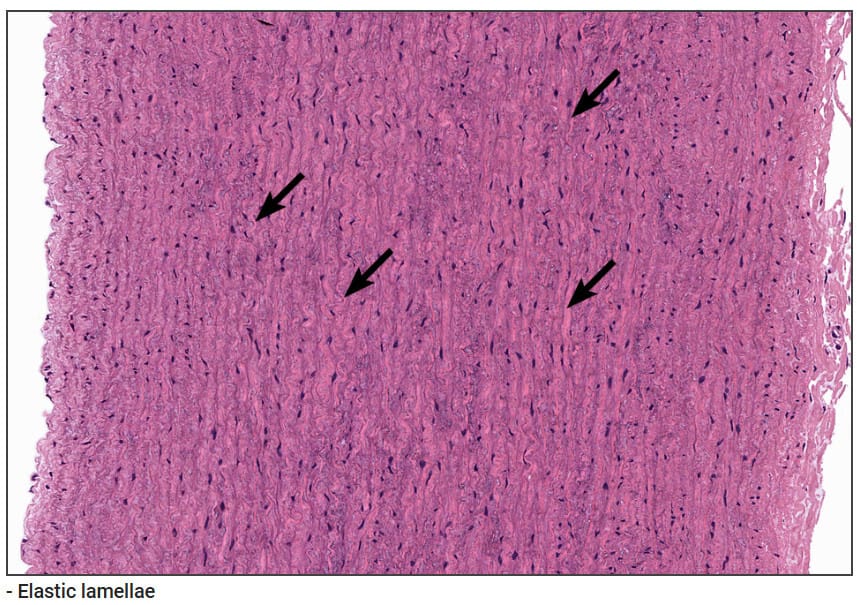

중막 (Tunica Media)

| 중막 (Tunica Media) |

| ✅ 중막은 탄성 동맥의 가장 두꺼운 층으로, 많은 수의 동심원형 탄성판(concentric elastic lamellae)과 그 사이를 잇는 민무늬근(smooth muscle cell)로 구성됩니다 |

| 대동맥의 경우 30~50층 이상의 탄성판이 존재하며, 이 층은 혈압의 변동을 흡수하여 혈류를 안정화하는 역할을 합니다. 섬유아세포와 교원질도 일부 포함됩니다. |